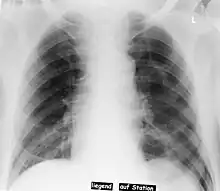

| Pneumothorax left sided | |

| Differential diagnosis | pneumothorax |

In radiology, the deep sulcus sign on a supine chest radiograph is an indirect indicator of a pneumothorax.[1][2] In a supine film, it appears as a deep, lucent, ipsilateral costophrenic angle[3] within the nondependent portions of the pleural space as opposed to the apex (of the lung) when the patient is upright. The costophrenic angle is abnormally deepened when the pleural air collects laterally, producing the deep sulcus sign.[4]

Patients with chronic obstructive pulmonary disease (COPD) may exhibit deepened lateral costophrenic angles due to hyperinflation of the lungs and cause a false deep sulcus sign.[4]